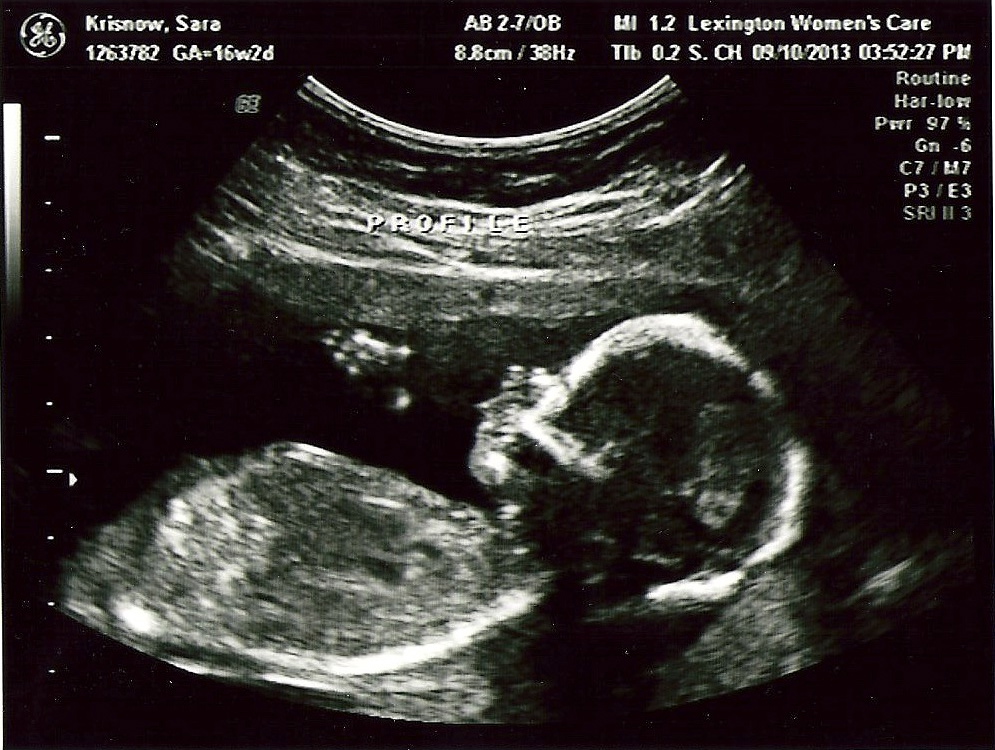

Месяц Беременности Фото Плода На Узи